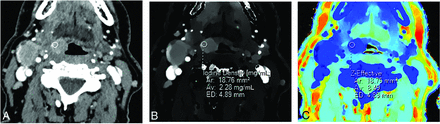

A 70-year-old man with left vocal cord squamous cell carcinoma (asterisk) and asymmetric sclerosis of the right arytenoid cartilage (arrowhead) seen on a conventional CT image (A). Iodine density (B), color iodine density overlay (C), and Z-effective (D) images reveal right paraglottic fat involvement with increased iodine density. The patient was upstaged from T2 to T3.